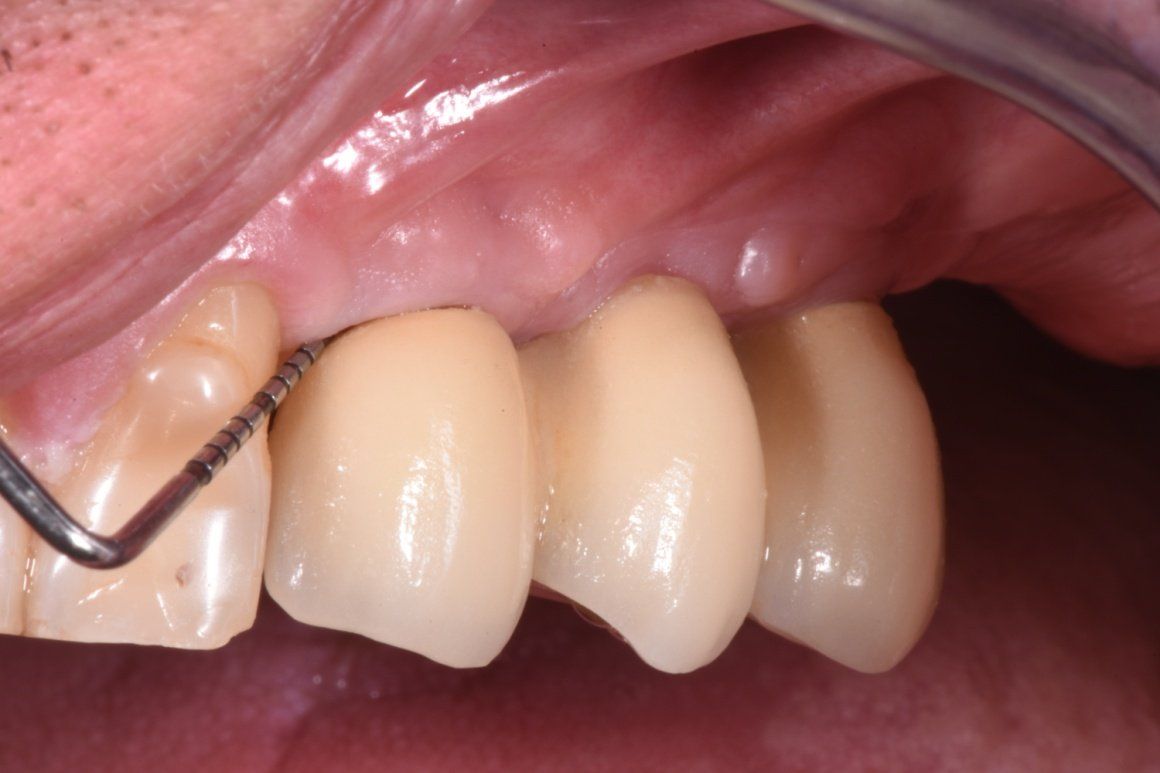

Il paziente selezionato per questo case report presenta 2 impianti dentali posizionati 4 anni prima in zona 23 e 25. Sono evidenziati al momento del primo appuntamento (T0) i segni clinici di mucosite con sanguinamento abbondante al sondaggio, presenza di gengiva infiammata e placca, mancanza di segni radiografici con perdita di osso marginale maggiore di 2 mm.

Il paziente, uomo di 55 anni non presenta nessuna patologia sistemica, non fuma e non assume farmaci in modo abitudinario, ma presenta dei segni clinici di infiammazione a livello del manufatto implanto-protesico su 2.3, nessun segno radiografico rilevante (Fig. 1).

Al primo appuntamento (T0) il paziente è stato visitato e sono stati rilevati i dati clinici, anamnesti e radiografici. L’anamnesi è negativa per patologie sistemiche. Una volta accertata la presenza di mucosite sull’elemento 2.3 al paziente vengono fornite le istruzioni per una terapia reattiva domiciliare, ovvero si consiglia l’uso di spazzolino con setole morbite unito ad un agente antimicromico e anti-infiammatorio, in questo caso a base di Nitradine. In particolare, la confezione di PerioTabs®, consiste di 10 compresse a base di NitrAdine® e un dosatore (Fig. 2). Tutte le sere per dieci giorni, dopo aver effettuato la normale igiene interprossimale con gli scovolini, il paziente deve far sciogliere una di queste compresse in un bicchiere con il dosatore pieno di acqua tiepida (Fig. 3), e immergere il nuovo spazzolino nella soluzione per circa dieci minuti, affinché le setole assorbano la soluzione (Fig. 4). Dopodiché, dovranno spazzolare denti e gengive nella zona da trattare, senza utilizzare dentifricio, per almeno due minuti (Fig. 5). Dopo il trattamento si risciacqua abbondantemente con acqua. Lo spazzolino deve essere usato per dieci giorni, alla sera, secondo le indicazioni riportate sulla confezione PerioTabs®, mentre al mattino i pazienti spazzoleranno i denti senza alcun dentifricio o soluzione (Fig. 6).

Dopo trenta giorni (T2) dalla prima seduta (T0), i pazienti tornano in studio per rivalutare i parametri clinici. Si può subito notare, clinicamente che il risultato estetico e l’aspetto clinico della salute tissutale è evidente a T2 come a T1 nonostante i giorni trascorsi. Una terapia non chirurgica suddivisa da un approccio domiciliare reattivo iniziale consente agli operatori di lavorare con maggiore predicibilità, ottimi risultati estetici e minimo dolore per il paziente; inoltre una terapia di supporto post-trattamento consente di mantenere il risultato di salute ottenuto nel tempo21.